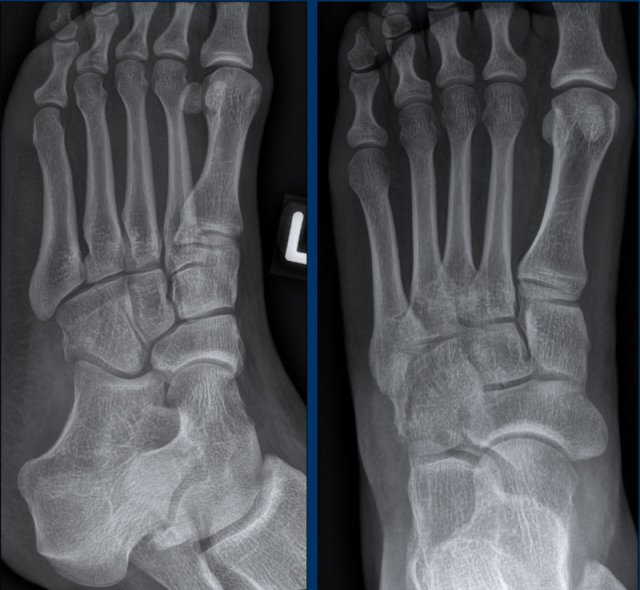

case 1 - foot distortion

33 year old patient with a foot injury and swollen midfoot.

What are the findings and what does it mean?